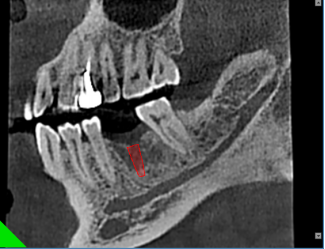

颌面外科扫描能精确展示特定解剖特点,如囊肿或牙断裂,深度牙根形状和倾斜度。

阻生病例1